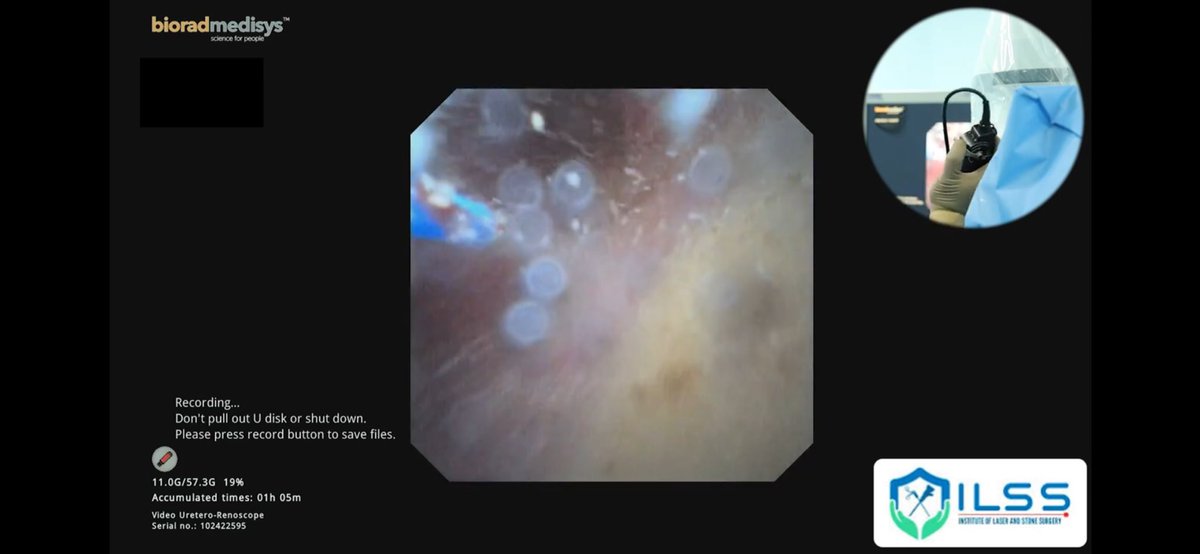

Primary RIRS for 15mm Pelvic stone in Ectopic Kidney. REDPINE 7.5F ureteroscope and JenaSurgical Ho YAG LASER used here. Short length Access sheath used(28 cm). #UroSome